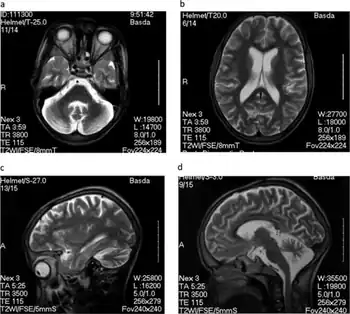

a,b)MRI axial brain and sagittal c,d) indicating cerebellar atrophy

Diagnosis is not very advanced and is based on the telltale nodding seizures of the victims. When stunted growth and mental disability are also present, probability of nodding syndrome is high. In the future, neurological scans may also be used in diagnosis.[17]